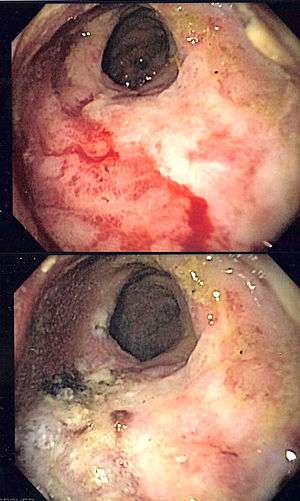

| Endoscopic image of radiation proctitis before and after therapy with argon plasma coagulation. | |